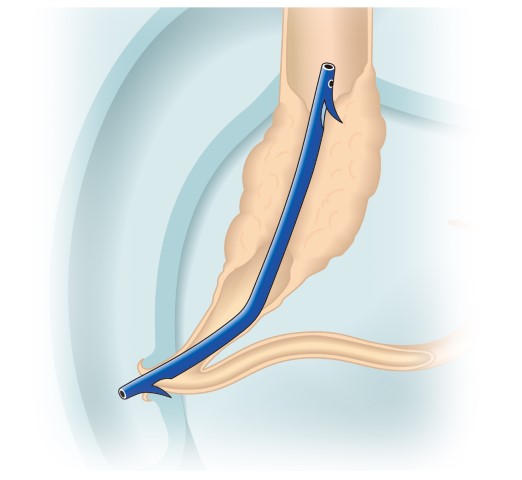

内視鏡的粘膜切除術(EMR)

外来にて切除することの出来ない、比較的大きめの大腸ポリープや平坦な病変などの切除の際に行います。

| 1:ポリープを見つけ、NBI併用拡大観察をした後、 | 2:ポリープ直下の粘膜下層に局注液を注入し盛り上げます。 | |

| 3:ポリープをスネアに通し、周囲の正常粘膜を入れて病変を絞扼 | 4:電気を流してして切除します。 | |

| 5:切除面をクリップで縫合閉鎖し、回収した検体の病理検査に提出します |